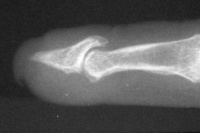

The tip graft progressively resorbed, and by six years after reconstruction, the hook nail deformity has recurred completely.

Image Image

Xrays over this period: initial deformity, bone graft, and progressive bone graft loss over the course of years: